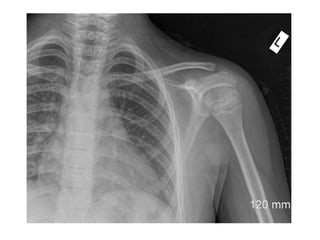

Shoulder Region

• 1st Year- Head of

humerus

• 2nd –Greater tuberosity

• 5th year- Lesser tub.

• 6th Year- Fusion of upper

end of humerus into one

mass

• FUSION

• 20th Year - Fusion of

upper end of humerus

with shaft

Shoulder Region • 1stYear- Head of humerus • 2nd –Greater tuberosity • 5th year- Lesser tub. • 6th Year- Fusion of upper end of humerus into one mass • FUSION • 20th Year - Fusion of upper end of humerus with shaft